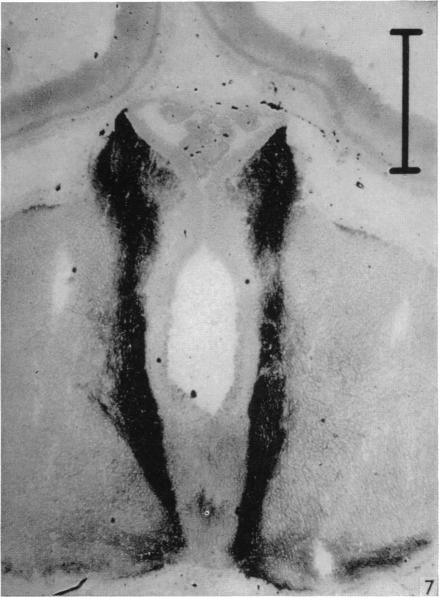

Acetylcholinesterase in the developing forebrain.

J Anat. 1966 Jan;100(Pt 1):63-89.